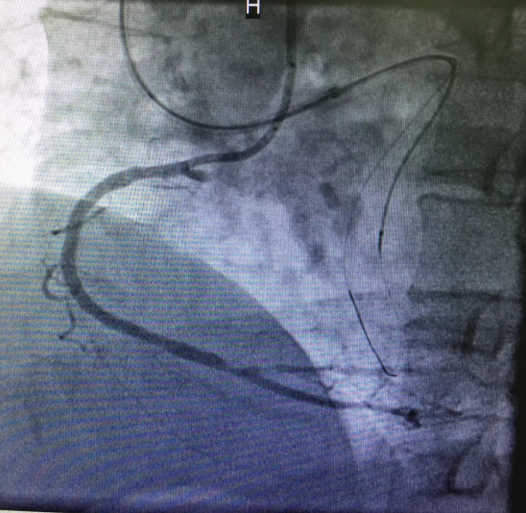

心内三完成成人导航首例逆向开通冠脉CTO病变